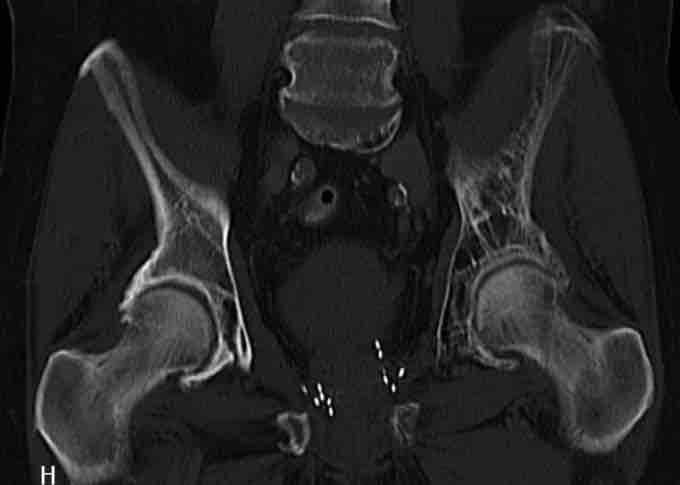

Paget's disease of bone is shown in the left pelvis. Notice the seeds in the prostate after brachytherapy.